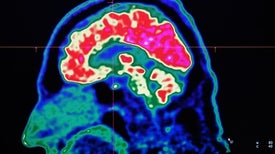

Functional neurological disorders are very real, and medical compassion is an important part of treatment